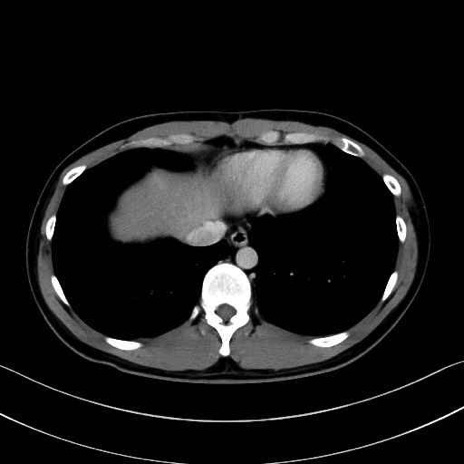

腰方形筋(quadratus lumborum muscle)のCT画像の解剖

1. 体幹部(腹部・背部・後腹壁)の筋肉

腹直筋 (Rectus abdominis)

外腹斜筋 (External oblique)

内腹斜筋 (Internal oblique)

腹横筋 (Transversus abdominis)

腰方形筋 (Quadratus lumborum)

広背筋 (Latissimus dorsi)

脊柱起立筋 (Erector spinae)

多裂筋 (Multifidus)